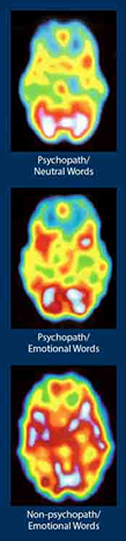

Hare, scanned brains while he exposed the subjects to emotional and neutral words. The results were the psychopaths' brain scans showed little change between neutral and emotional words. Indicating much less brain activity as compared to the non-psychopaths' brain scans, which showed more activity for emotional than neutral words. See scans.